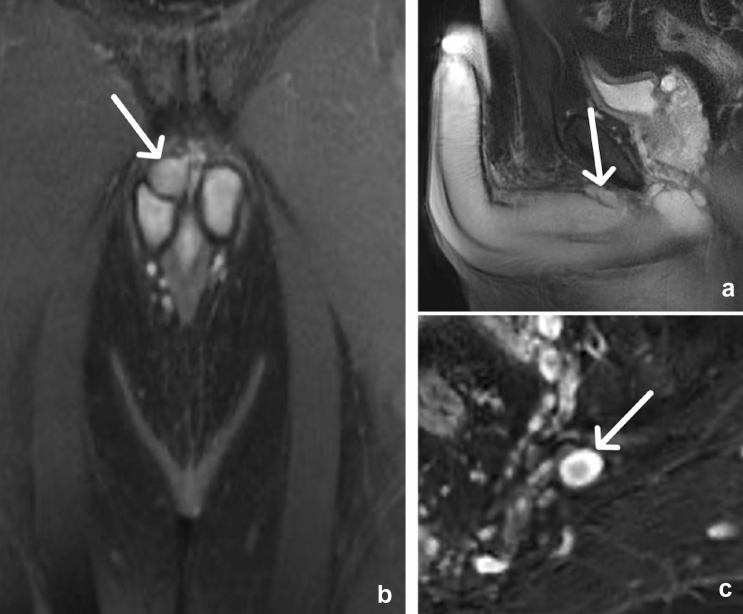

Fig. 8.

36-year-old male with Neurofibromatosis type I demonstrating a penile and multiple additional sacral neurofibromas. Sagittal (a) and coronal (b) T2W fat-saturated MR images demonstrate an elongated mass with high signal intensity in the dorsal aspect of the penis (arrow). Axial (c) T2W fat-saturated images reveal additional ovoid masses of the sacral plexus which demonstrate the “target sign” appearance, with high peripheral signal intensity and low central intensity (arrow)

Given the large number of exiting spinal nerves in the abdomen and pelvis, peripheral nerve-sheath tumors are commonly encountered. Schwannomas and neurofibromas can be found anywhere along a peripheral nerve, and these two histologically distinct tumors share many imaging features. These tumors are usually less than 5 cm in diameter and on MRI have slightly greater signal than muscle on T1W images and exhibit high signal on T2W images. The “target sign,” where the center of the tumor is low in signal on T2W images with a peripheral rim of a high signal, is most often seen with neurofibromas (Fig. 8). Histologically, a central fibro-collagenous core and surrounding myxomatous tissue account for this imaging pattern. The target sign may also be seen in schwannomas; however, in these lesions, it is due to a central distribution of the more cellular Antoni type A cells, with a surrounding rim of hypocellular Antoni type B cells. Loss of a previously seen target sign in a peripheral nerve sheath tumor is concerning for malignant transformation. The tumor sometimes appears to have a “tail” on either side, representing the entering and exiting nerve [15, 16]. While these are benign tumors, they may exhibit locoregional mass effect and may show heterogeneous enhancement (Fig. 9).